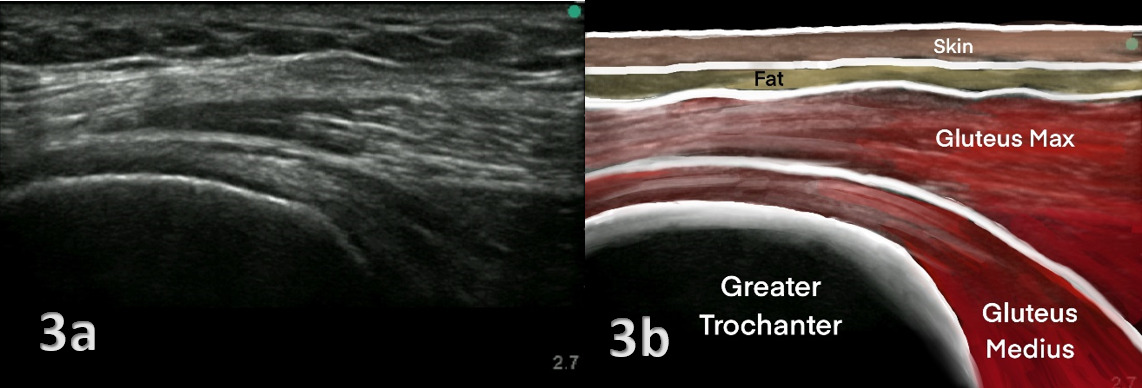

O diagnóstico é clínico e considera história, exame físico (palpação do trocânter, testes de abdução resistida e single-leg stance) e avaliação funcional. Exames de imagem podem ser usados para confirmação ou casos persistentes:

- Ultrassonografia: pode mostrar tendinopatia/rupturas; é operador-dependente.